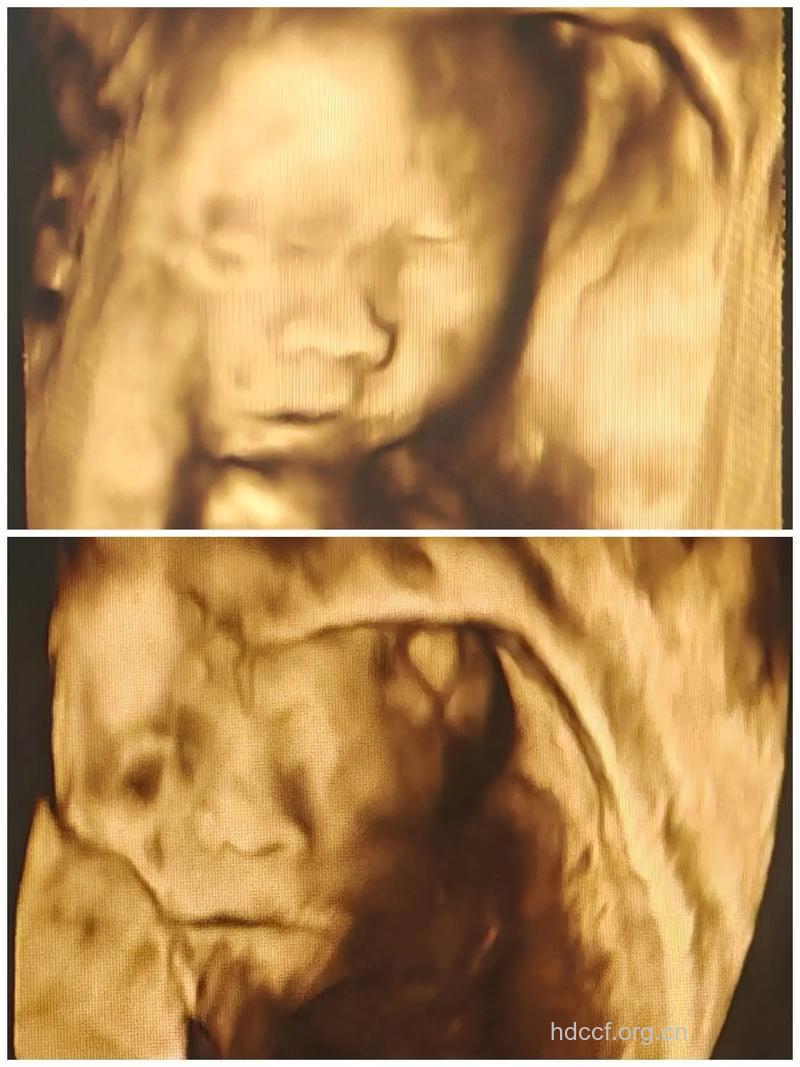

足月宝宝的平均身长为50.8厘米,体重为3.2千克,随时有可能临产,胎儿肺脏的发育已经成熟,全身开始长皮下脂肪,身体变成圆形的,皱纹也少了,皮肤呈有光泽的颜色,长满全身的细毛开始逐渐消腿,脸上和肚子上的细毛已经消失。